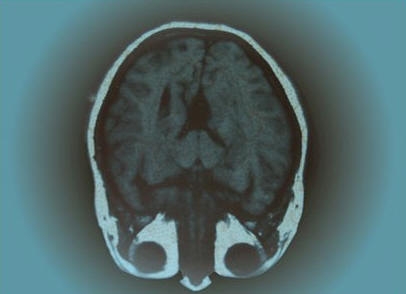

Schädel-Röntgenbild

AMagnetresonanz-Tomografie